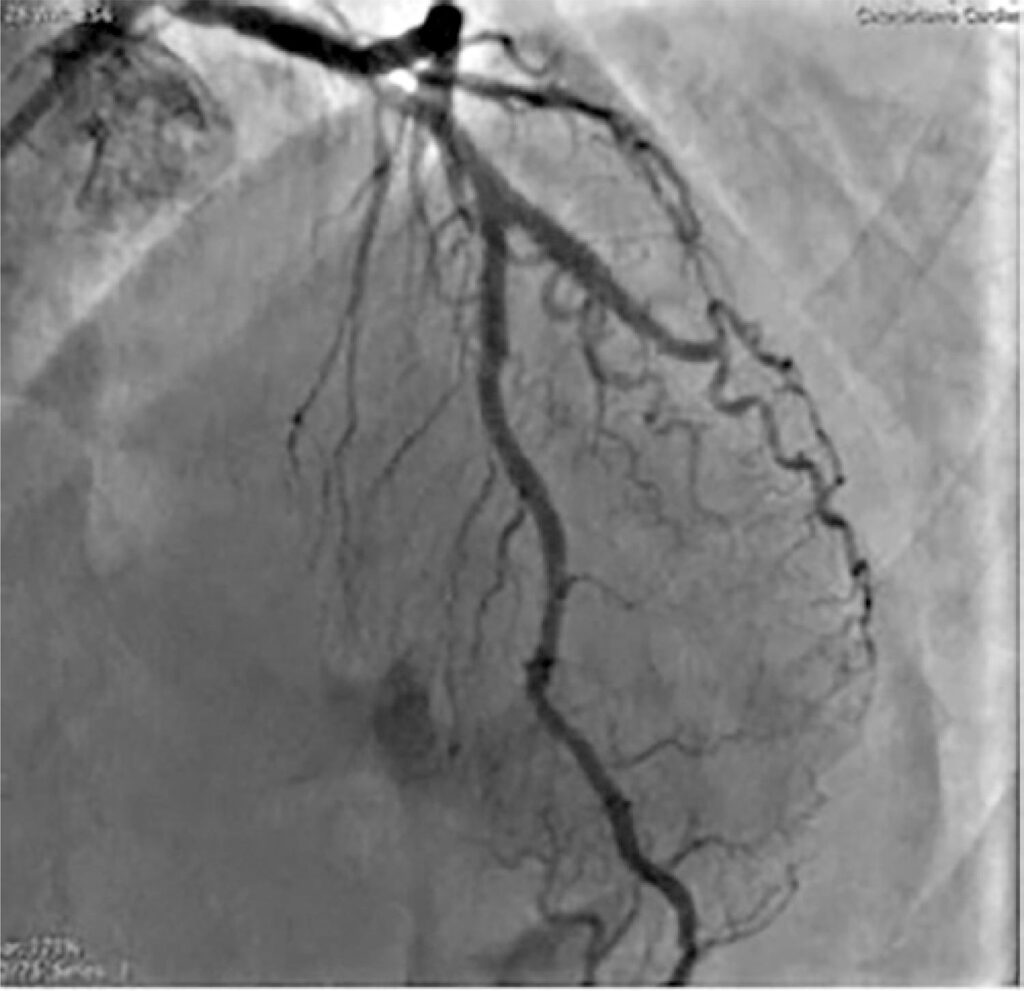

Treatment of in-stent restenosis lesions, especially calcified lesions, with stent underexpansion, generally requires more complex techniques, such as rotational atherectomy. The case reported is a male patient with a 99% in-stent focal restenosis lesion at the origin of the first diagonal branch, where two stents were implanted 14 years ago. After failure of balloon angioplasty alone, ablation of the plaque and part of the stent struts was performed using the rotational atherectomy technique, which allowed the implantation of a new stent which was totally expanded.